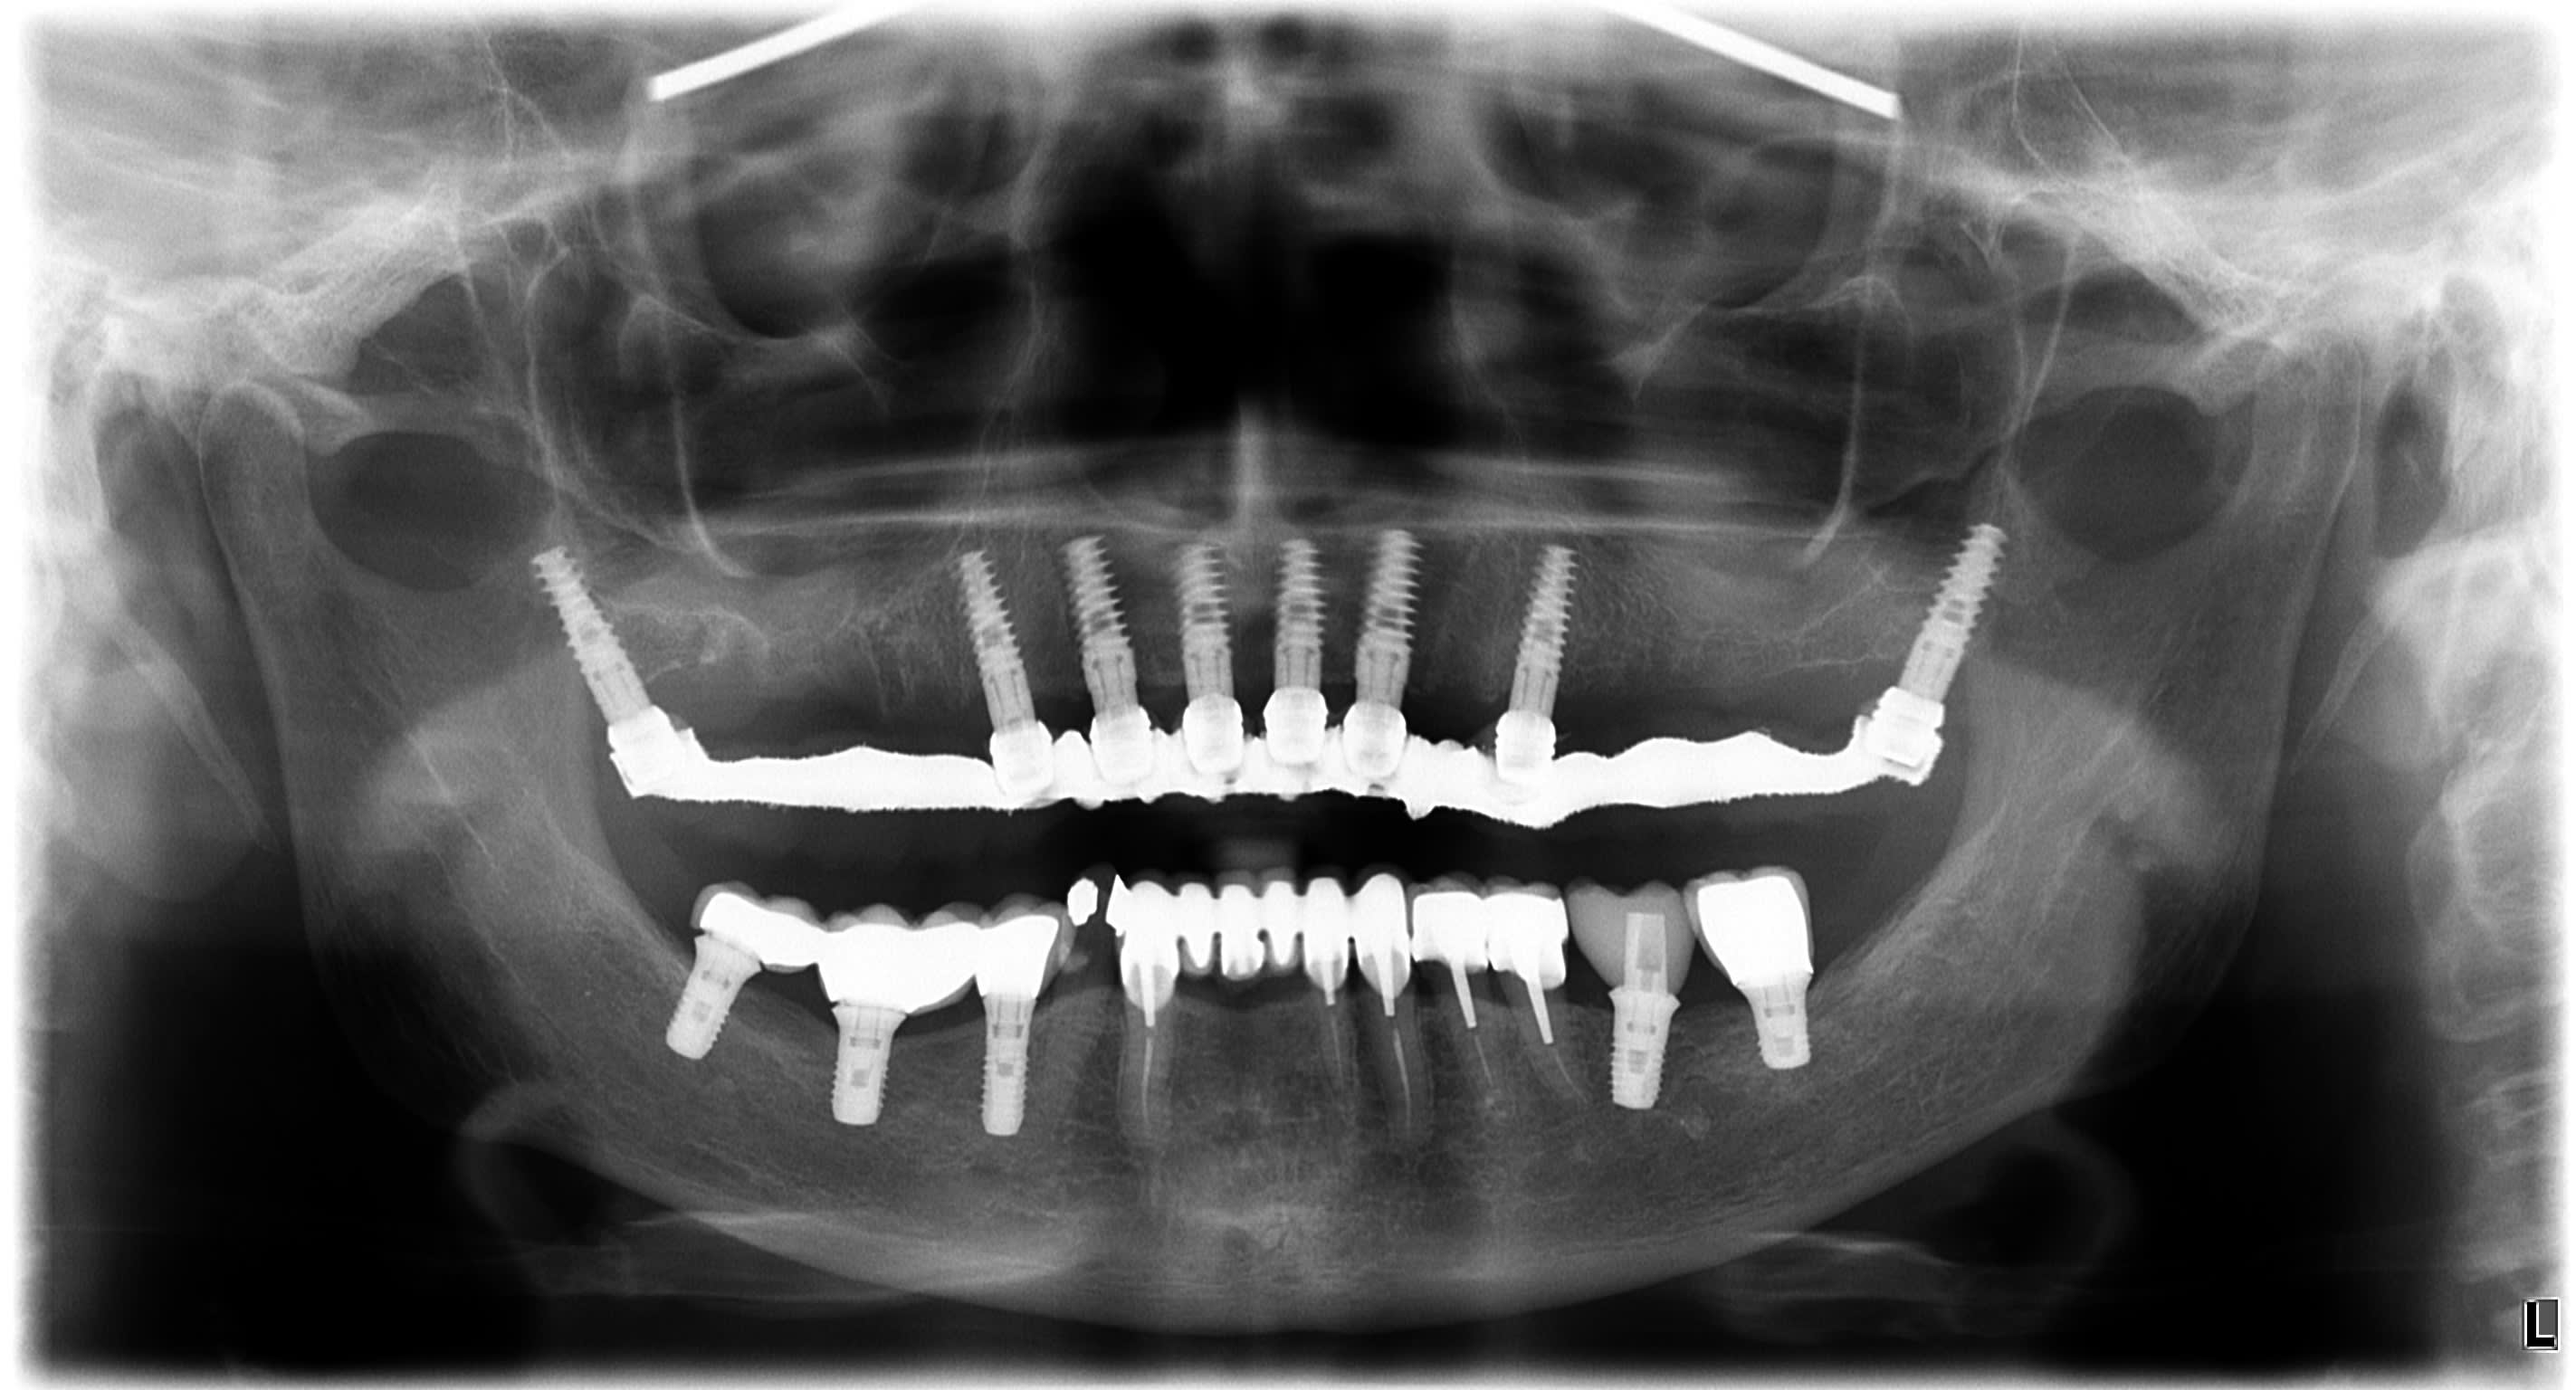

qualité d'image....je te laisse juger une pano (exportée en jpeg donc tu perds en définition), çà vaut tous les commentaires....

le On Demand 3D....pas très compliqué à prendre en main si tu connais un peu les logiciels de planification implantaire....

Kavo3d jl6avh - Eugenol